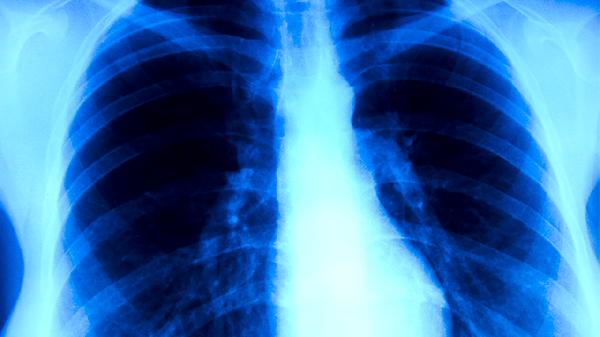

肺结核可能通过体检发现,但普通体检项目可能无法直接检出肺结核。肺结核主要通过胸部X线检查、痰涂片检查、结核菌素试验等方法诊断,常规体检若未包含这些项目则难以发现。

普通体检通常包括血常规、尿常规、肝功能等基础项目,这些检查无法直接诊断肺结核。部分体检套餐包含胸部X线检查,可能发现肺部异常阴影,但需结合痰检或结核菌素试验进一步确诊。肺结核早期症状不典型,可能仅出现低热、乏力等非特异性表现,易被忽视。体检时若未主动告知医生结核病接触史或疑似症状,漏诊概率更高。

肺结核确诊需依赖专业检查。痰涂片找抗酸杆菌是诊断开放性肺结核的金标准,结核菌素试验可辅助判断感染状态,胸部CT能更敏感地发现早期病灶。对于高危人群如密切接触者、免疫力低下者,即使体检结果正常,出现咳嗽咳痰超过两周也应专项筛查。部分非活动性肺结核或肺外结核,常规体检更难发现。